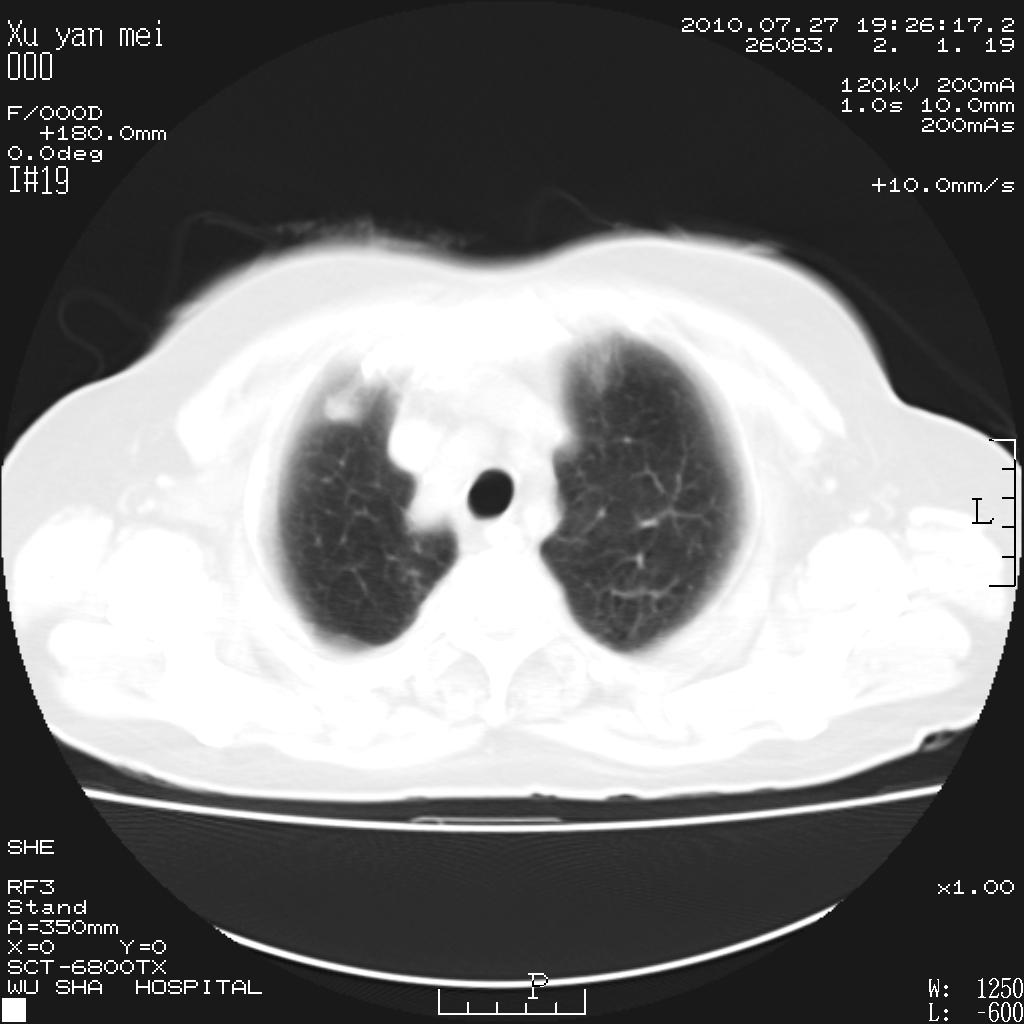

女,60岁,胸痛就诊,右肺结核?炎症?其它?(胸片右侧中上肺野确实看不到什么啊)

1)考虑两肺感染性病变;建议抗炎治疗后复查。2)双侧少量胸腔积液。

1)考虑两肺感染性病变;建议抗炎治疗后复查。2)右侧少量胸腔积液。

双肺炎症可能性大,建议抗炎后复查。右侧胸腔少量积液。双侧胸膜轻度增厚。

考虑两肺感染性病变;不除外肺栓;建议抗炎治疗后复查。